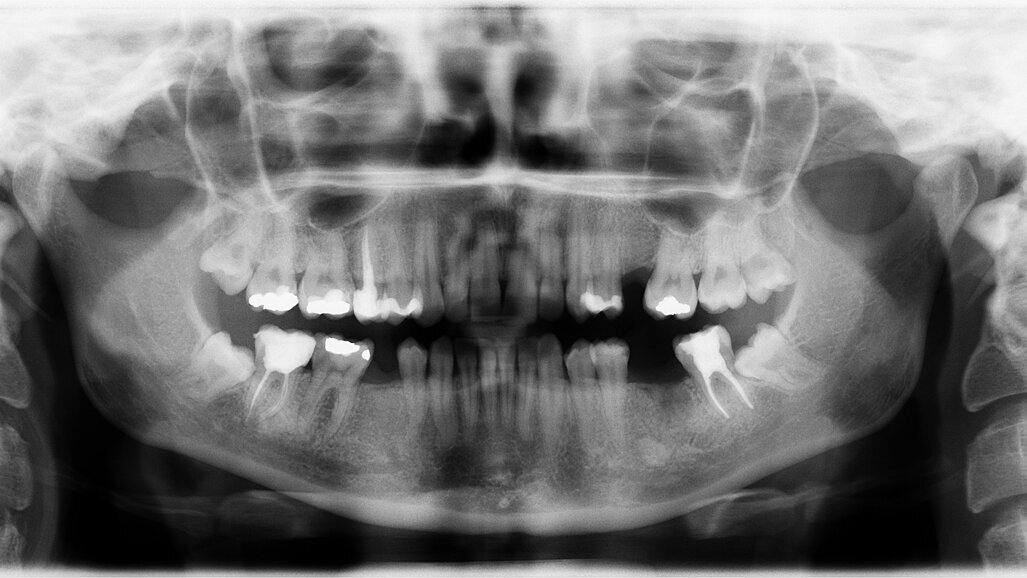

W 2023 r., wychodząc naprzeciw potrzebom lekarzy dentystów, Ośrodek Szkolenia Naczelnej Izby Lekarskiej, zorganizuje specjalistyczne kursy z radiologii. W dn. 31.03.-2.04.2023 r. odbędzie się pierwszy w tym roku bezpłatny Kurs Ochrony Radiologicznej typu S. Szkolenie jest niezbędne do uzyskania uprawnień Inspektora Ochrony Radiologicznej.

Szkolenie prowadzone będzie zgodnie z Rozporządzeniem Ministra Zdrowa z dn. 14 października 2021 r. w sprawie nadawania uprawnień inspektora ochrony radiologicznej sprawującego wewnętrzny nadzór nad przestrzeganiem wymagań ochrony radiologicznej w jednostkach ochrony zdrowia. Szkolenie jest podstawą do uzyskania uprawnień Inspektora Ochrony Radiologicznej w pracowniach stosujących aparaty rtg w celach medycznych.

Uprawnienia typu S dotyczą nadzorowania działalności wyłącznie w zakresie stosowania aparatów rtg stomatologicznych lub do densytometrii kości.